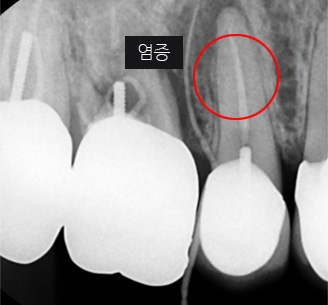

충치가 심해져 세균이 이 신경관까지 침투하면 심한 통증과 함께 염증이 생기고 치아뿌리까지 염증이 내려와 치아가 흔들리고 최후에는

치아를 잃게 됩니다. 그렇게 되기 전에 오염된 신경관을 치료하고 생체친화적 치과재료로 신경관을 채워주는 근관치료(신경치료)를 시행합니다.

지속적인 통증과 잇몸염증

기존 포스트 제거 후 근관내 약재 삽입

재 신경치료(난이도 상)